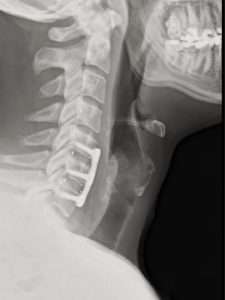

Saminder Singh of The Body Alignment Clinic in Essex, England, posted the update on Saturday. The Instagram post included photos of Ospreay undergoing treatment and an X-ray showing surgical screws in his neck vertebrae.

Another photo shows the surgical entry scar in Ospreay’s throat.